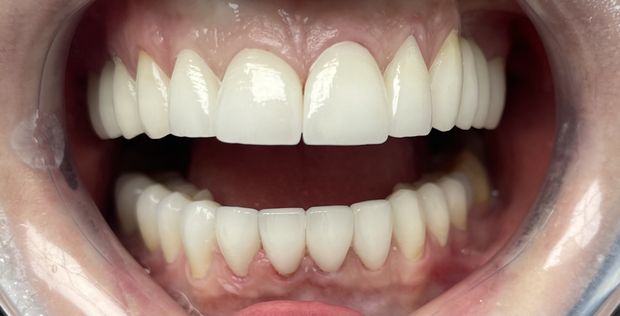

Pełna rekonstrukcja łuków zębowych, podwyższenie zgryzu, odbudowa utraconych tkanek zębów z wykonaniem koron cyrkonowych licowanych ceramiką oraz ruchomych uzupełnień protetycznych.